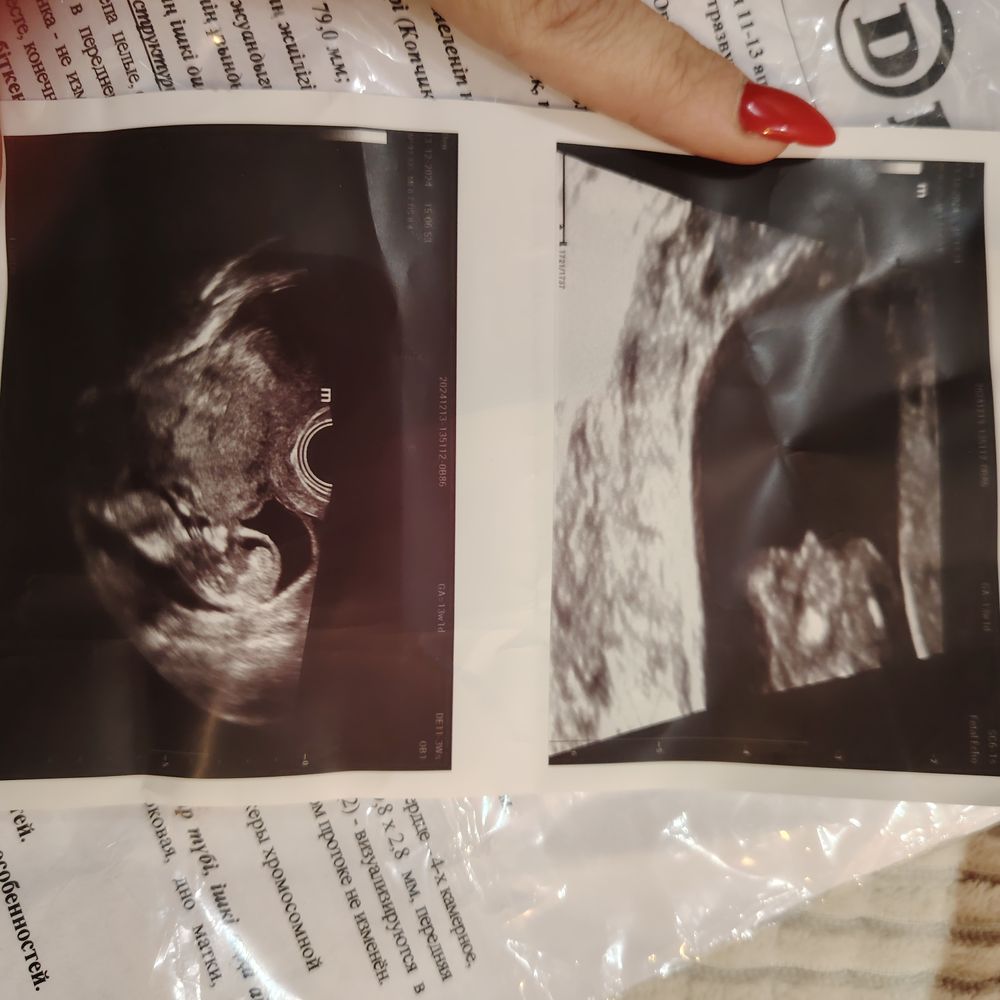

Алена, Изображение Изображение

Алена, Изображение Изображениевот скрин с видео ещё есть) Изображение

Ирина Качанова, я склоняюсь к девочке) а есть снимок с узи с 6-8 неделю?